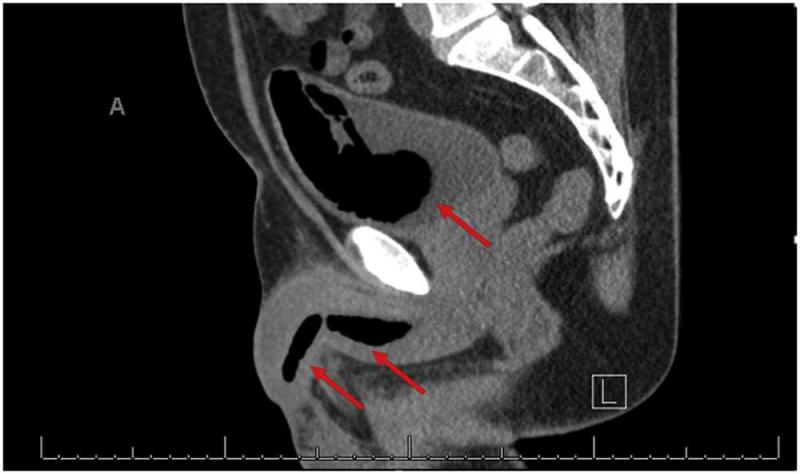

In het ziekenhuis wees een CT-scan uit dat het schuim tot helemaal boven in zijn plasbuis was gekropen en zelfs in zijn blaas was terechtgekomen. De man moest verschillende operaties ondergaan om al het isolatieschuim uit zijn lichaam te verwijderen. Ook bleek zijn plasbuis al flink versmald door littekenvorming, waarschijnlijk als gevolg van eerdere ingebrachte voorwerpen in zijn geslachtsdeel. De auteurs van het wetenschappelijk artikel benadrukken dat mensen die voorwerpen in hun plasbuis steken dat vaak herhaaldelijk doen, en vaak mentaal kwetsbaar zijn en kunnen lijden aan borderline. Ook zoeken (en vinden) sommigen op die manier seksueel genot.